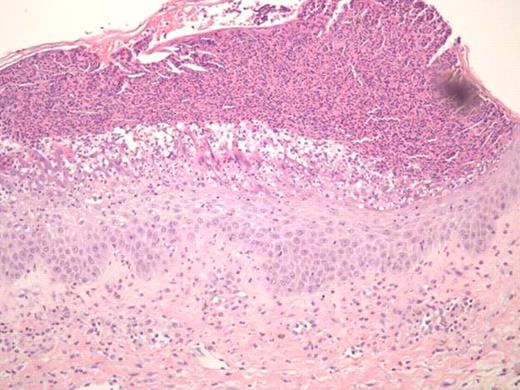

Treatment of sclerodermatous chronic graft versus host disease (cGVHD) remains a daunting challenge. Despite developments in prophylaxis for cGVHD, supportive care measures remain as the primary mode of therapy, with little evidence of treatments that reverse the process. Steroids and immunosuppressants are often ineffective, and extracorporeal photopheresis has been used with varying success. Recently, case reports have reported on the successful use of imatinib in treating sclerodermatous GVHD (Moreno-Romero et al, 2008; Leonardo Magro et al., 2009). We report a case of a 40-year-old male patient with extensive sclerodermatous cGVHD. In 2005 he underwent an unrelated stem cell transplant (SCT) for chronic myeloid leukemia. His transplant course was complicated by thrombotic thrombocytopenic purpura (TTP) associated with all standard immunosuppressive drugs (cyclosporine, tacrolimus and sirolimus). Two years later, the patient developed sclerodermatous GVHD and was given plaquenil, steroids, and photopheresis to manage this complication. Unfortunately, after months of treatment, he showed progressive disease, including increased contractures, and difficulties with inspiration. Based on case reports, and the patient's tolerance of imatinib prior to SCT, he was started on imatinib for his sclerodermatous GVHD. Within 5 days he developed generalized erythema, pustular rash, and skin sloughing (Figure 1). He was hospitalized for this severe reaction and was treated with high dose steroids after which, his symptoms began to improve. Resolution of erythema did not occur until months following initial exposure. Histological differential diagnosis included pustular psoariasis and Sneedon-Wilkinson syndrome. The skin biopsy revealed subcorneal pustular dermatosis (Figure 2). In view of this history, it is suggested that the exanthematous pustulosis was induced by imatinib in this patient. We recommend that close attention is paid to patients with cGHVD who are treated with imatinib and to intervene early in those who develop severe cutaneous reactions by stopping imatinib and starting appropriate therapy.

SEQ - skin biopsy revealing subcorneal pustular dermatosis